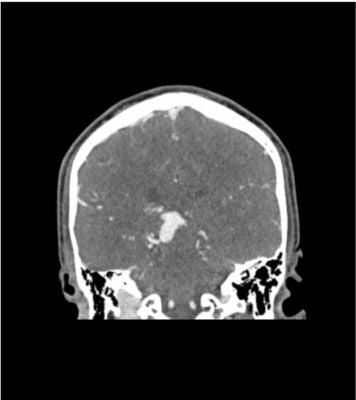

This phantom simulates a contrast medium-enhanced head in the arterial phase (CT angiography). It covers the vertex to the foramen magnum.

The phantom has 10 low-contrast lesions in the centrum semiovale and the right hemisphere has an arteriovenous malformation.

• Arteriovenous malformation of the right hemisphere.